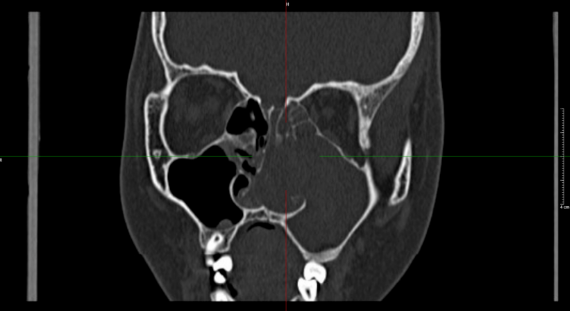

为求进一步规范治疗,家长带她来到济南南郊医院。耳鼻喉科杨钦龙主任接诊后,经详细专科检查,发现小患者左侧鼻腔存在单侧进行性鼻塞、流涕、反复出血情况,右侧鼻腔被出血性息肉完全占据,已致鼻中隔偏曲,鼻窦骨质结构受累、形态改变,具备手术干预指征。

术中,杨主任凭借精湛操作技术与丰富临床经验,精准切除患者鼻腔内肿物,同时对慢性鼻窦炎、肥大性鼻炎进行有效矫治。术后病理结果为出血坏死性息肉,明确病因。目前,患者恢复态势良好,鼻塞、流涕等症状明显缓解,嗅觉逐步恢复,有望摆脱长期鼻腔疾病困扰,回归健康生活。